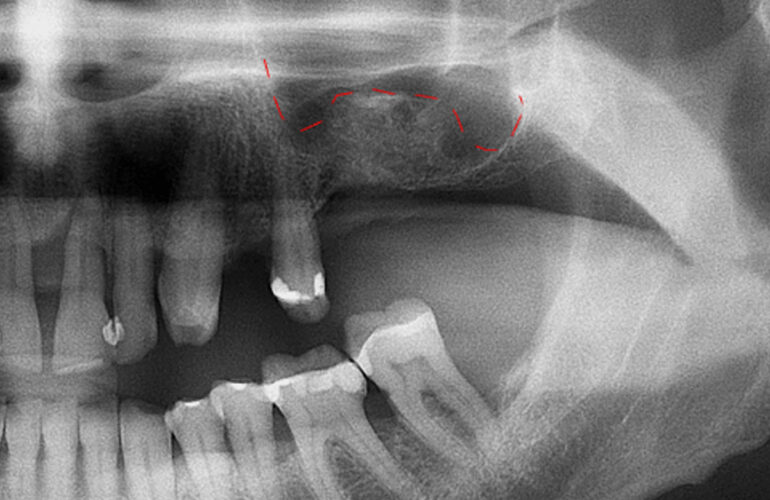

Grazie a TAC 3D e software avanzati, l’intervento viene studiato al computer prima di essere eseguito.

• Maggiore sicurezza: analisi dettagliata delle strutture anatomiche.